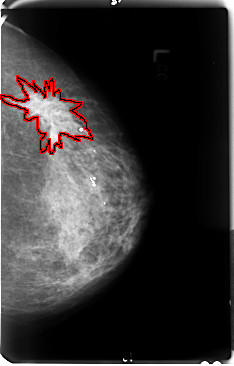

FILE: B_3048_1.LEFT_MLO.OVERLAY

TOTAL_ABNORMALITIES 1

ABNORMALITY 1

LESION_TYPE MASS SHAPE IRREGULAR-ARCHITECTURAL_DISTORTION MARGINS ILL_DEFINED-SPICULATED

ASSESSMENT 4

SUBTLETY 4

PATHOLOGY MALIGNANT

TOTAL_OUTLINES 1

BOUNDARY